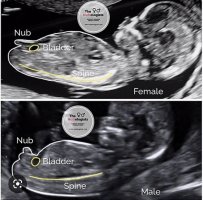

Er personen som tar ultralyd dyktig og godt kjent med nub, så kan kjønnet sees fra 12+5.Fikk innkallelse til tul idag 47 laaaange dager å venteEr det noen som vet om man kan få vite kjønn på tul?

Man skal likevel ta det med en bitte liten klype salt. Likevel oppgis det aldri kjønn om det er et snev usikkerhet

Hvis jeg har talt riktig, så vil jeg være 13,5uke daEr personen som tar ultralyd dyktig og godt kjent med nub, så kan kjønnet sees fra 12+5.Man skal likevel ta det med en bitte liten klype salt. Likevel oppgis det aldri kjønn om det er et snev usikkerhet

Om du ikke alt har gjort det, sett deg litt inn i nub teorien, kanskje du klarer å se det selv

Kanskje litt dumt spørsmål…AbsoluttOm du ikke alt har gjort det, sett deg litt inn i nub teorien, kanskje du klarer å se det selv

Absolutt ikke et dumt spørsmålKanskje litt dumt spørsmål…Hva er nub teorien?